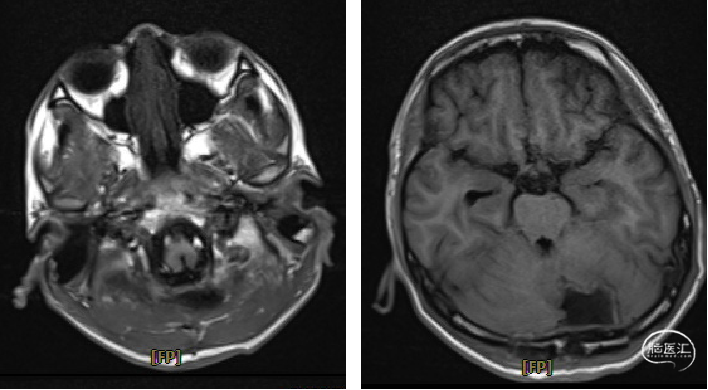

术前检查

术前CT

术前MRI

image.png

诊断及手术方式

术前诊断:

1.小脑、延髓占位(血管母细胞瘤)

2.梗阻性脑积水